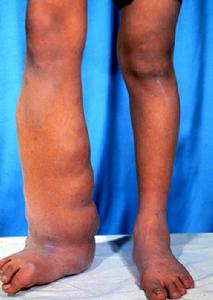

神經纖維瘤神經纖維瘤病是顯性遺傳引起的一種神經外胚葉異常。軟纖維瘤兒童發病,軀幹及四肢近端為主多發性數毫米至數厘米的半球狀或帶蒂的腫瘤,柔軟,皮色、粉紅色或褐色,隨年齡增多增大,成年發展較慢。象皮病樣多發性神經纖維瘤的皮損常沿神經乾分布,多發,為皮內及皮下軟性結節、斑塊。約10%患者產生惡變,特別是生長快、較大的損害,損害發展成神經纖維肉瘤。咖啡斑,常見於軀幹,特別在腰背部,數公分大小的褐色斑片,卵園形,境界清楚。少數患者口腔出現乳頭狀瘤,巨舌。近半數者智力發育不良,顱內腫瘤及癲癇發作。成年病情發展較快及皮損較大者因惡性變預後不良。

神經纖維瘤分為多發性神經纖維瘤和局部神經纖維(或神經纖維瘤)兩種。多發性神經纖維瘤:腫瘤為多發性,多者達數百個,可在全身各處生長。大小不一,小的如豆粒,乳頭大小,大的如雞蛋,生長緩慢。大的多突出於體表,也可成片、成塊的生長,使皮膚和皮下層肥厚、下垂、起褶呈橡皮狀。腫瘤柔軟,無觸痛,皮膚常有程度不一的色素沉著。此病大多自幼年已發生,可能有先天性因素,有的伴有智力遲鈍,某些器官畸形。經常受壓迫或摩擦的腫瘤,可能會發生惡性變,故妨礙較大的腫瘤可作切除。局部神經纖維瘤或神經鞘瘤,多數是單發,也可以是數個瘤體沿神經乾生長,多見於腋窩,肘側和頰部等處。瘤體開始時為硬結,逐漸增大,表面光滑,與皮膚不粘連,質地堅硬。當腫瘤擠壓神經本身時,可產生自發痛、麻木、觸痛、感覺過敏或遲鈍等症狀。這些改變的範圍和該神經乾支配區域一致。局部神經纖維瘤應施行手術切除。

腫塊呈多發性、數目不定,少的幾個,多的可成百上千難以計數。小的如米粒,大的似拳頭,甚至可達十數公斤以上。可鬆弛地懸掛於皮表,皺褶及鬆弛可致畸形明顯。神經纖維瘤沿神經乾的走向生長時呈念珠狀,或蚯蚓塊狀形結節。此外神經纖維瘤皮膚可出現咖啡斑,大小不一,形如雀斑小點狀,或大片狀,分布與神經纖維瘤腫塊的分布無關。腫瘤數目不多的患者,皮膚色素咖啡斑狀沉著是纖維神經瘤的重要診斷之一。本病多發於軀幹,有時出現於四肢及面部,患者常合併許多疾病應予重視加以區別。